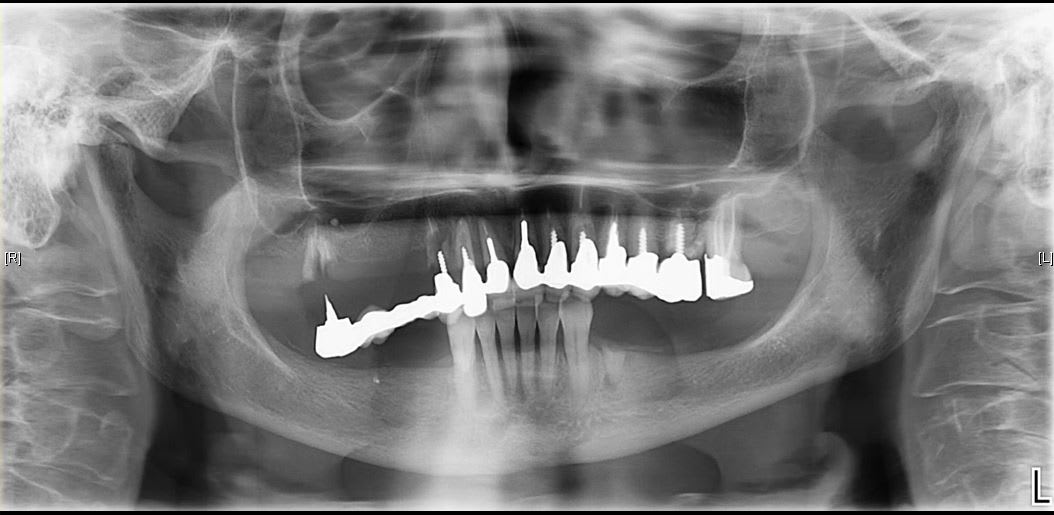

Qui est un pro du all on four ici?

Et ne laissez pas ça vous détourner du "6 on 2" au maxillaire, je vous laisse imaginer le porte à faux...

gabzou tu mis la barre trop haute d'un coup

all on four 15 dents respect

pas compris pourquoi il n' y a pas d'extension en 38